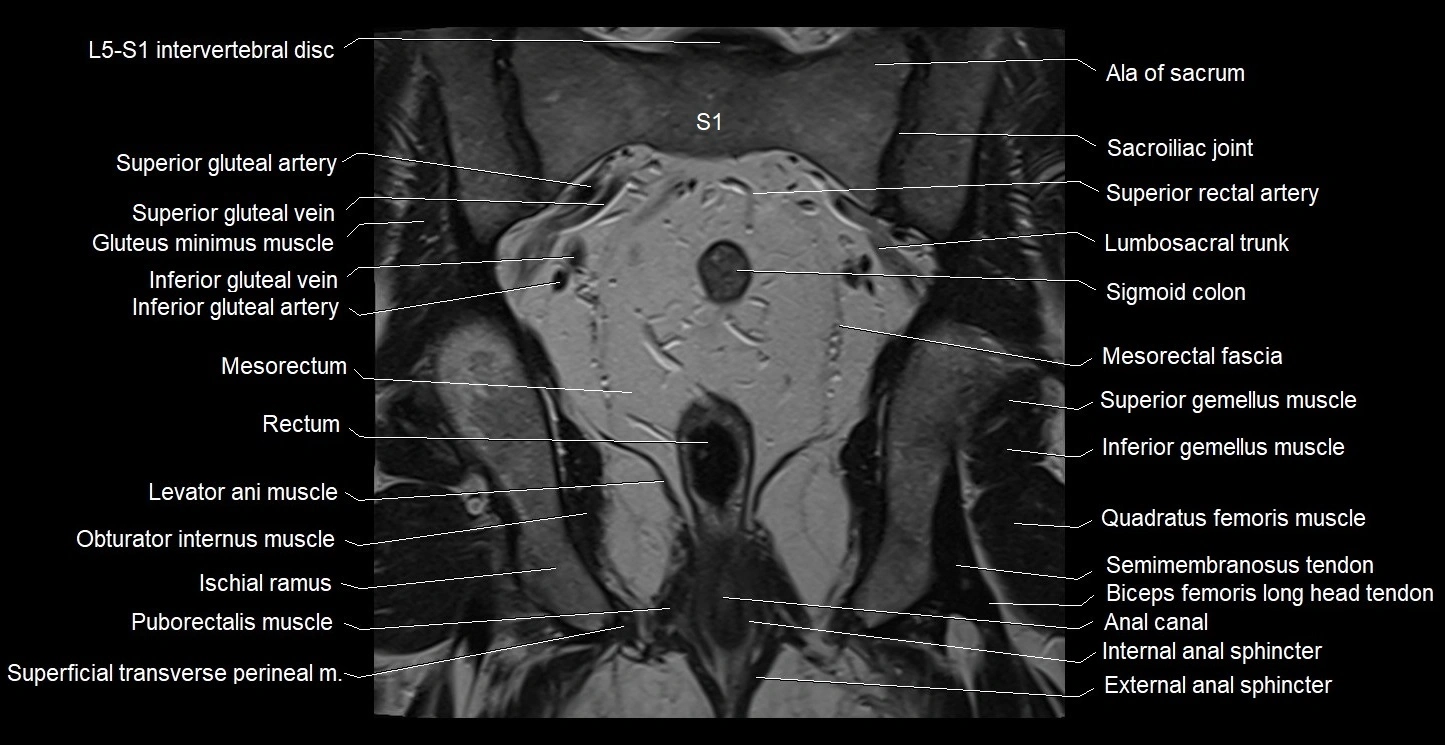

- Ala of sacrum

- Anal canal

- External anal sphincter

- Inferior gemellus muscle

- Inferior gluteal artery

- Inferior gluteal vein

- Internal anal sphincter

- Internal iliac vein

- Levator ani muscle

- Mesorectal fascia

- Mesorectum

- Puborectalis muscle

- Rectum

- Sacroiliac joint

- Semimembranosus tendon (proximal)